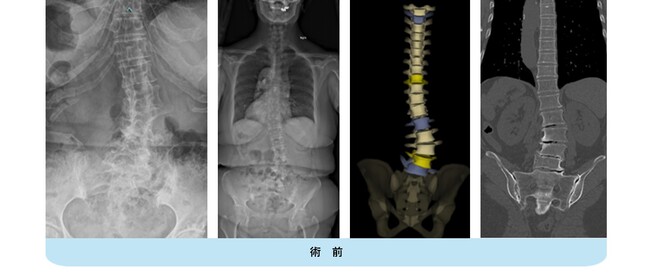

40代の女性です。中学生の時に側弯を指摘されて装具治療を行っていましたが、途中で通院をやめてしまったようです。最近腰痛が顕著となり、仕事や日常生活に支障が出てきたため来院されました。著しい側弯変形を認め、側面では胸腰椎移行部の腰曲がりが既に出現しています。

腰椎側方経路椎体間固定術と後方矯正固定術を2回に分けて行い、下位腰仙椎の固定術を回避して生理的な姿勢、側弯の改善が得られました。腰痛は無くなり、仕事も痛みなく出来るようになりました。